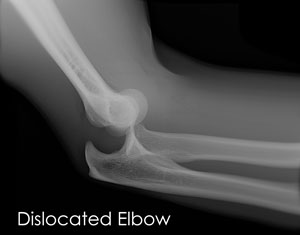

To diagnose elbow dislocation Professor Bain will examine your arm, check the pulses at the wrist and will evaluate the circulation to the arm. An X-ray is necessary to determine if there is a break in the bone.